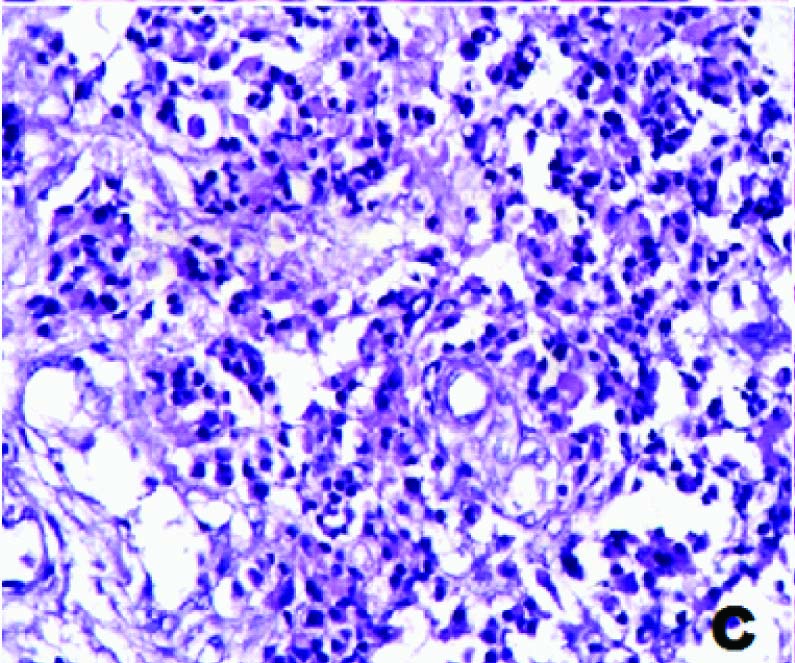

A 55-year-old male patient presented with pain abdomen and multiple skin nodules over the anterior abdominal wall and left cervical lymphadenopathy. On local examination, the abdominal skin nodules were firm to hard in consistency and the largest measured 3 x 2 cms. The left cervical lymph node was single, discrete and firm to hard in consistency. FNAC was performed on the abdominal skin nodules and the left cervical lymph node. FNAC smears studied from both the left cervical lymph node and the abdominal skin nodules showed similar cytological features. The smears were highly cellular and showed predominantly dispersed cell population of uniform tumour cells [Table/Fig-1a] in sheets, clusters, rosettes and tumour balls [Table/Fig-1b]. The cytoplasm was moderate, eosinophilic and granular. The nuclei were round to oval, with stippled chromatin and inconspicuous single prominent nucleolus [Table/Fig-1c]. Plenty of atypical mitoses were present [Table/Fig-1d]. In addition, many multinucleated giant cells and bizarre tumour cells were seen. Extracellular eosinophilic basement membrane- like material was also seen [Table/Fig-2a].

FNAC showing tumour cells with eosinophilic cytoplasm and fine nuclear chromatin (H&E,×1000)

Sections from the supraglottic growth revealed hyperplastic stratified squamous epithelium and a tumour in the subepithelium which was composed of monomorphic tumour cells arranged predominantly in diffuse sheets separated by fibrovascularseptae [Table/Fig-2b]. Occasional rosettes and trabecular patterns were observed. The tumour cells had moderate eosinophilic cytoplasm, round nuclei with fine chromatin and inconspicuous nucleoli. A few bi and multinucleated tumour giant cells were also seen. Foci of vascular invasion were seen.

Histopathology showing tumour cells separated by fibrovascular septa (H&E,×400)

Sections from the abdominal skin nodules showed a subepithelial, infiltrating, malignant tumour with monomorphic cells arranged in sheets, nests, organoid, trabecular and mosaic patterns [Table/Fig-2c,2d]. They exhibited moderate degree of pleomorphism at places [Table/Fig-3a]. The cells had moderate to abundant granular cytoplasm and nuclei with salt and pepper type of chromatin [Table/Fig-3b]. The tumour cells were arranged in rosette- like fashion. Focal, large areas of necrosis were seen [Table/Fig-3c].